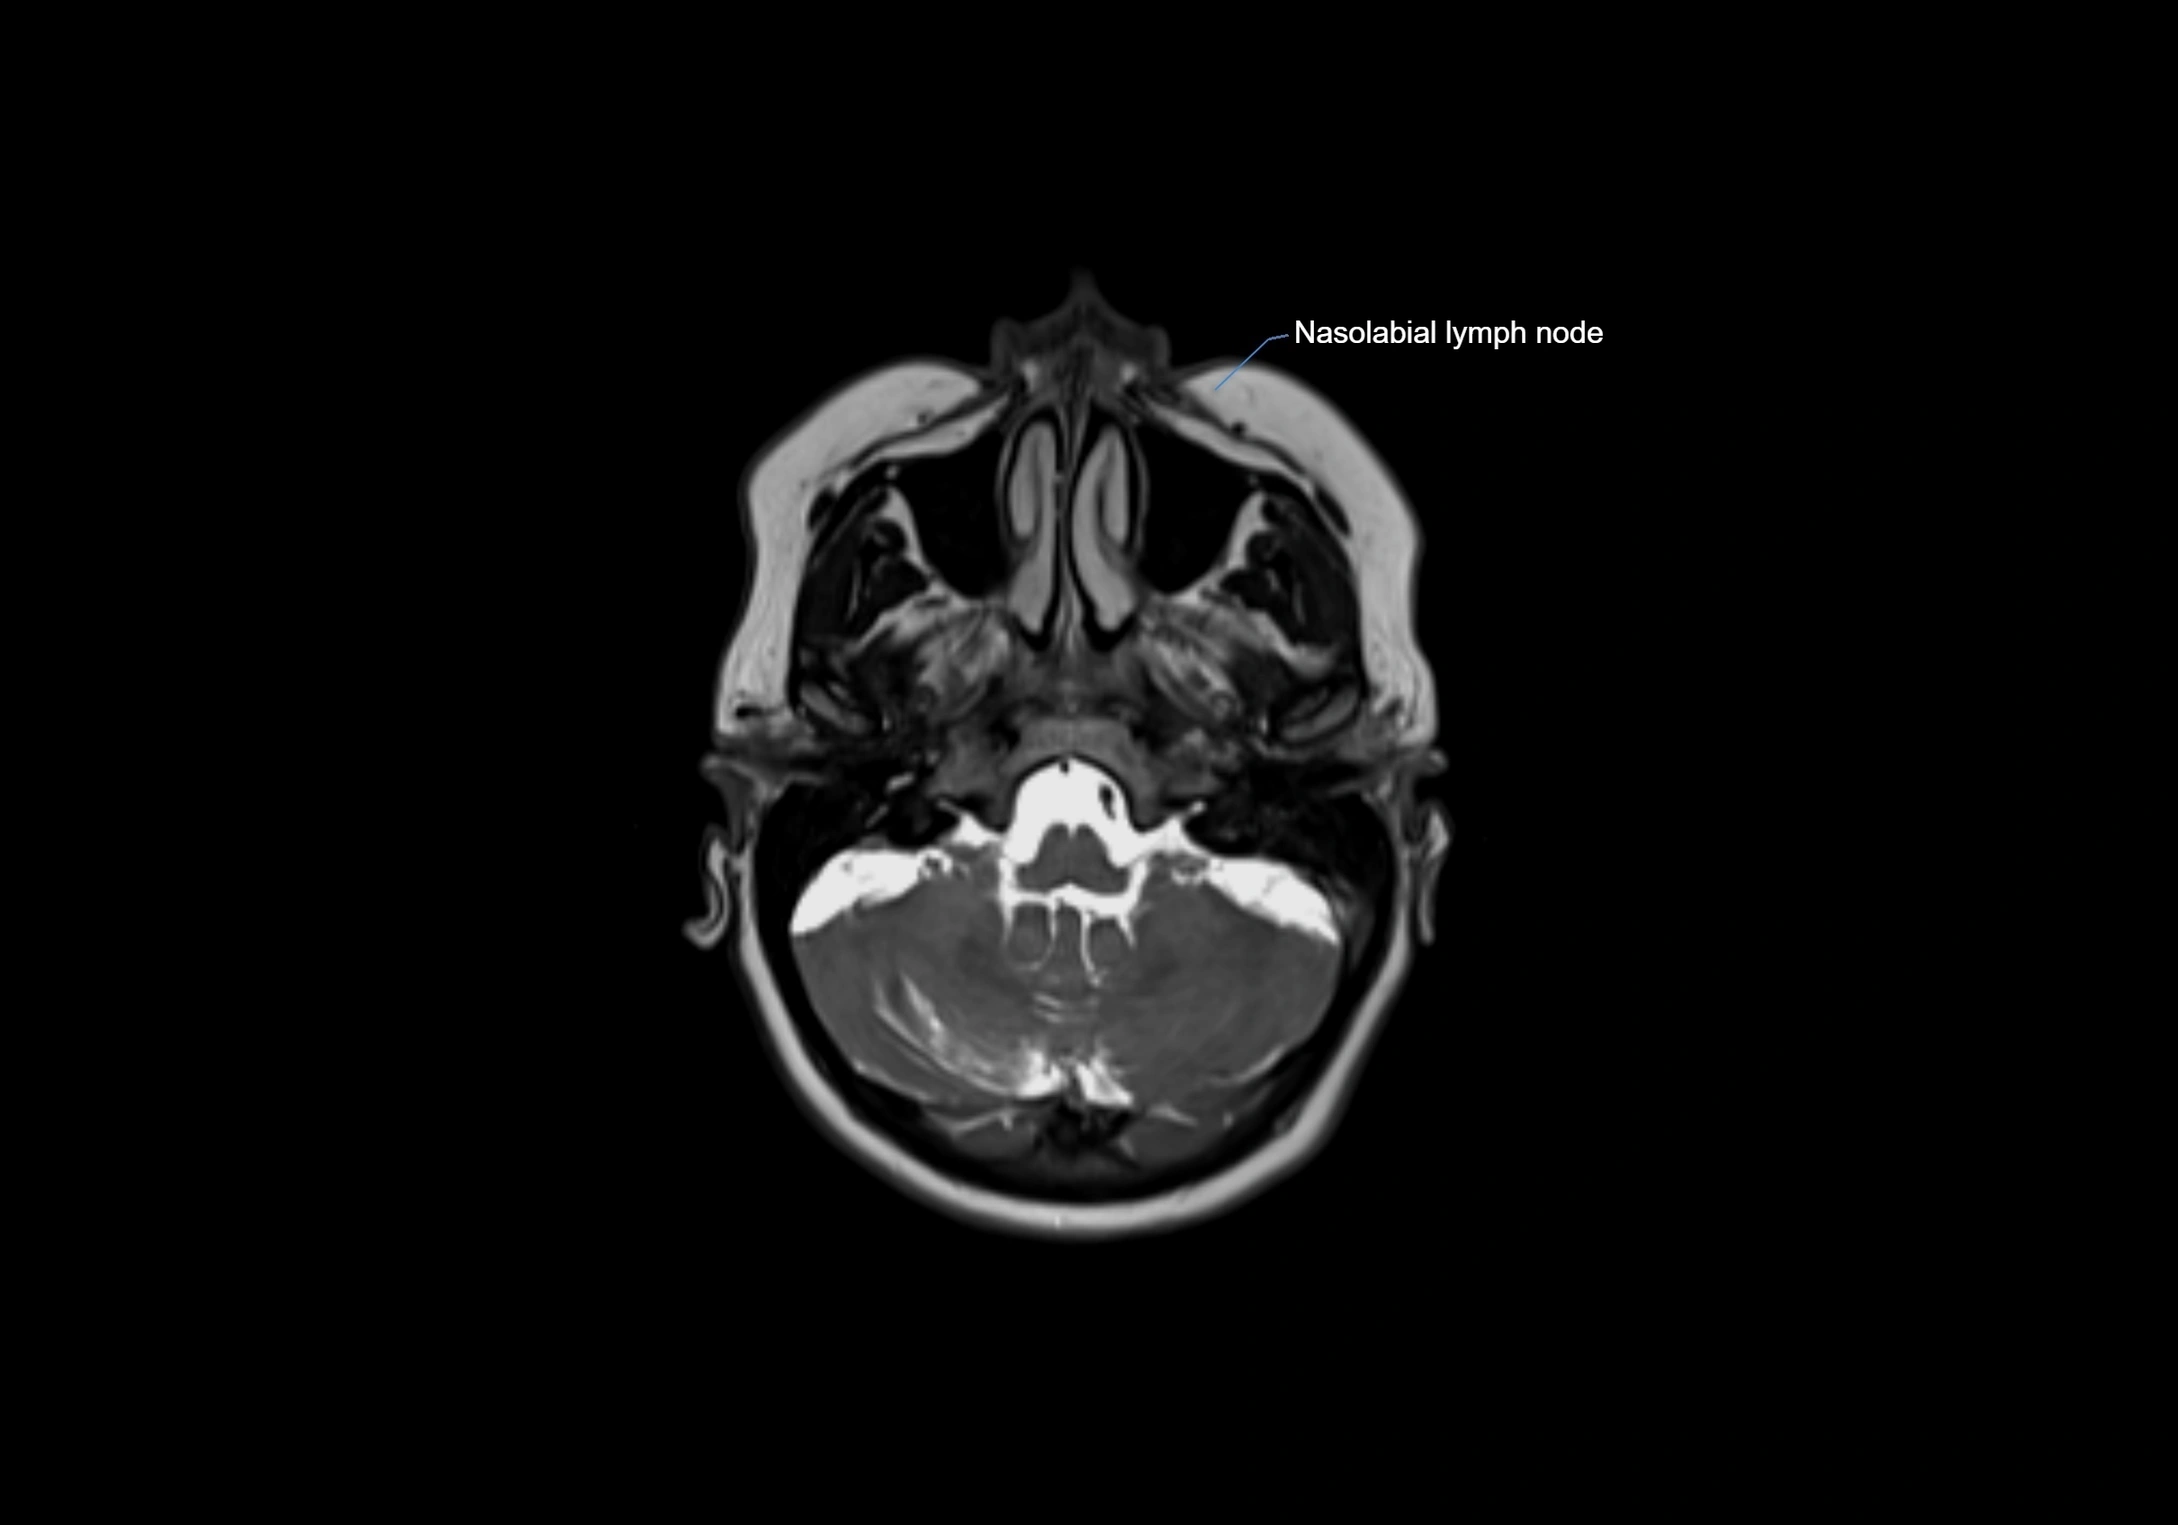

MRI Appearance

T1-weighted images:

• Normal accessory nodes appear as small, oval hypointense to intermediate signal structures within subcutaneous fat

• Surrounded by hyperintense fat, enhancing contrast for visualization

• Pathological nodes may appear enlarged or rounded, sometimes with cortical thickening

T2-weighted images:

• Nodes show intermediate signal, with surrounding fat bright

• Useful for detecting edema, inflammation, or infiltration

• Fatty hilum may appear slightly hyperintense relative to cortex